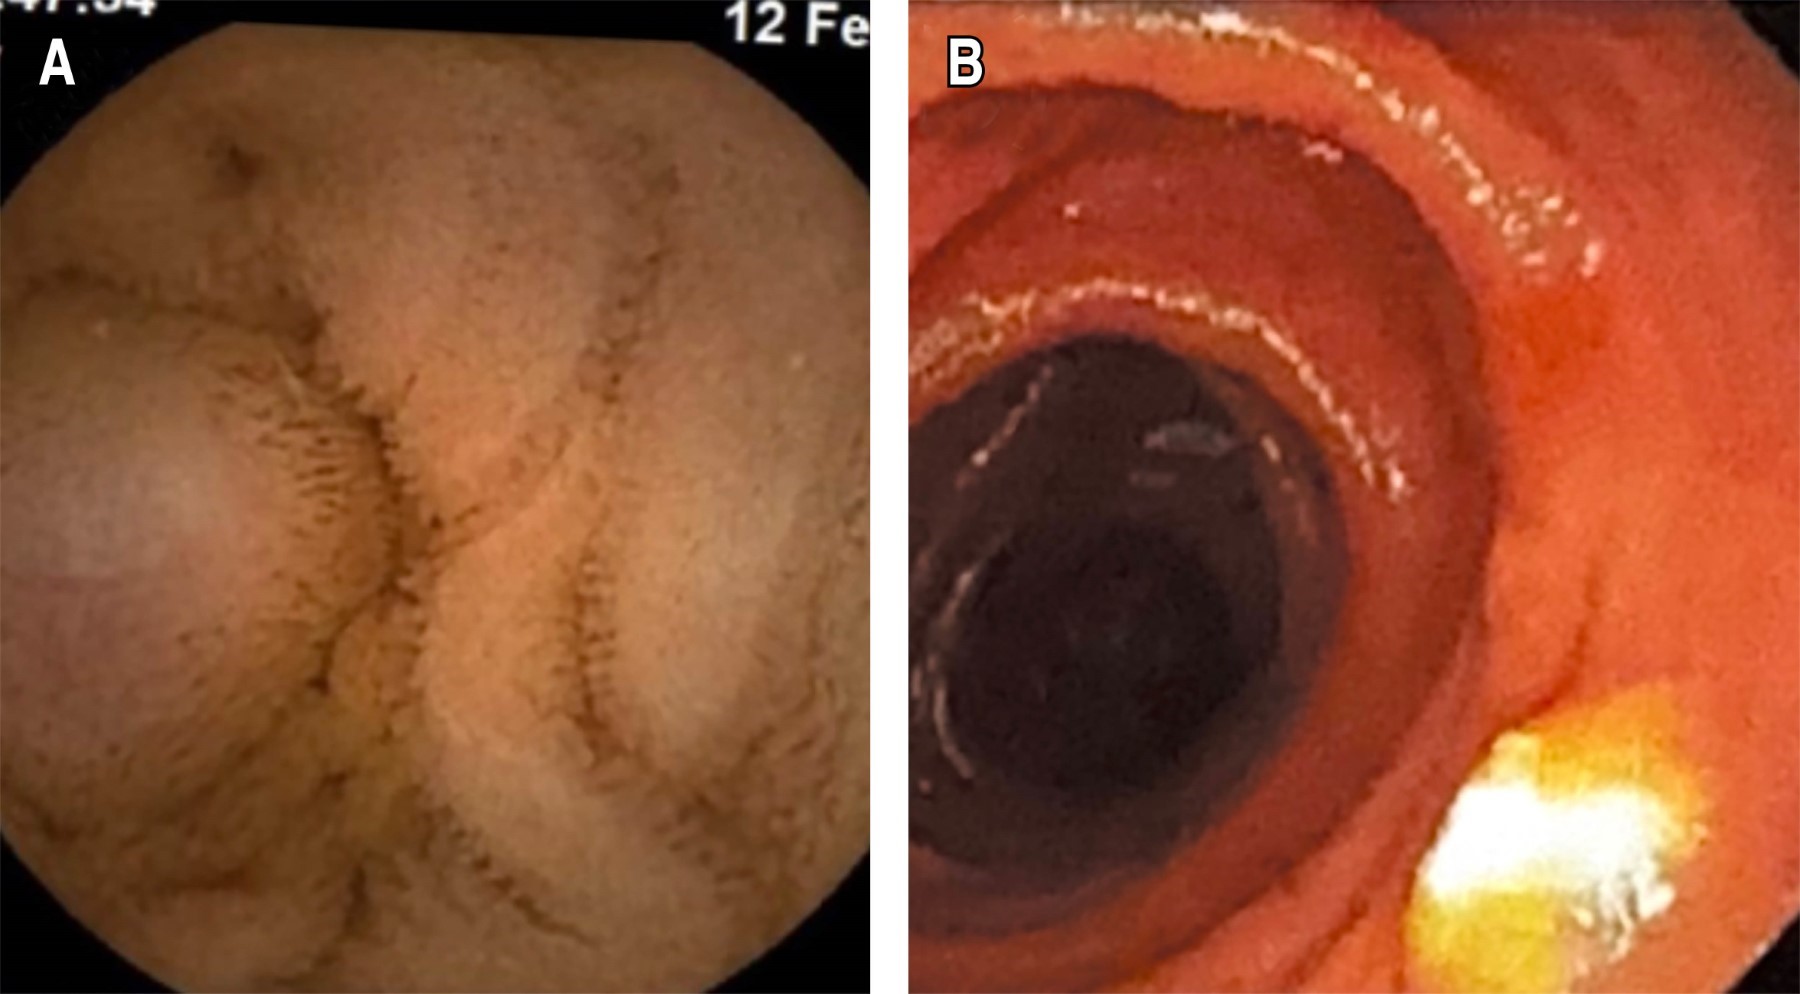

Complete diagnostic protocol in a patient with GIST

Gastrointestinal bleeding is a medical emergency that requires immediate attention, considering age and comorbidities. Symptoms range from anemia to melena. It uses panendoscopy as an initial evaluation method. If this is negative, use capsule endoscopy. Gastrointestinal stromal tumors are mainly benign, although 30% are malignant, located in the stomach and small intestine. The first-line intervention treatment is surgical resection and imatinib as therapy. We describe the case of a 51-year-old female patient admitted for burning and colic epigastric pain, nausea, pallor, and multiple melena stools. We transfuse two red blood cell concentrates. After clinical deterioration, different tests were performed, including capsule endoscopy to identify non-visible bleeding and enteroscopy to mark the lesions detected through the capsule. We performed a diagnostic laparoscopy where a subepithelial tumor of the proximal jejunum was identified and resected. Histopathological analysis reveals a low-risk gastrointestinal stromal tumor with negative margins. We referred the patient to oncology for follow-up. Tests such as capsule endoscopy and enteroscopy allow identification of the origin of bleeding in the mid-gastrointestinal tract, as described in this report.

Figure 1

Figure 2